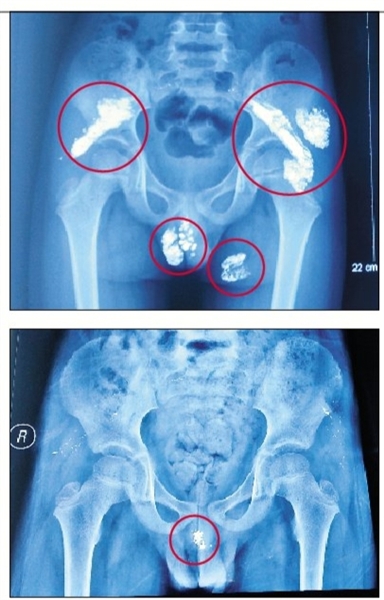

奇奇入院时(上图)及手术后的X光片(下图),圈中为汞显影。

今年2月5日,于先生带奇奇来到昆明医科大学第一附属医院照X光片。X光片显示,奇奇的臀部两侧有大量的金属物质。医生诊断,这些金属物质为汞(俗称水银)。检测得知,奇奇尿汞含量超标1万多倍。

体内尚残余原来1%汞

昨日下午,307医院儿科主任何玺玉介绍,5岁的奇奇刚来医院时,非常虚弱,体重不到30斤。医院接诊后,通过查体发现,奇奇臀部、阴囊、双侧髂骨下等全身多处发现大量软组织包裹液态汞。这些汞在奇奇体内至少已经存留5个月以上,奇奇臀部皮肤出现破溃、引起高烧等诸多并发症,甚至出现生命危险。

院方介绍,经过两个疗程的内科驱汞和手术,奇奇体内血汞含量已降到正常值,抢救治疗工作取得阶段性成功。目前,奇奇体内阴囊部分还残余原来的1%左右汞,“在不影响病情和发育前提下,医院会对奇奇作进一步观察和研究”。同时,院方表示,奇奇已于5月出院。之所以现在才通报诊治过程,是因涉及云南当地警方破案保密工作的需要,不便过早公布相关信息。